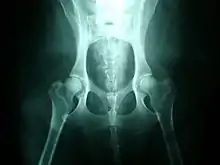

La gravedad de la displasia se puede medir si trazamos el denominado ángulo de Norberg. Éste consiste en trazar sobre una radiografía una línea que vaya desde el centro de una cabeza del fémur, al centro de la otra. Posteriormente, desde ambos extremos se traza otra línea que pase por el borde acetabular dorsal, formando así un ángulo con la anterior. Según la amplitud del ángulo, tenemos que:

- No se presenta displasia si es mayor de 105º.

- Si mide entre 100-105º, el animal tiene displasia leve.

- Si mide entre 90-100º, la displasia es moderada. Se acompaña de enfermedad degenerativa articular y aplanamiento del acetábulo.

- Si mide menos de 90º, la displasia es grave. Puede llegar a presentar luxación.